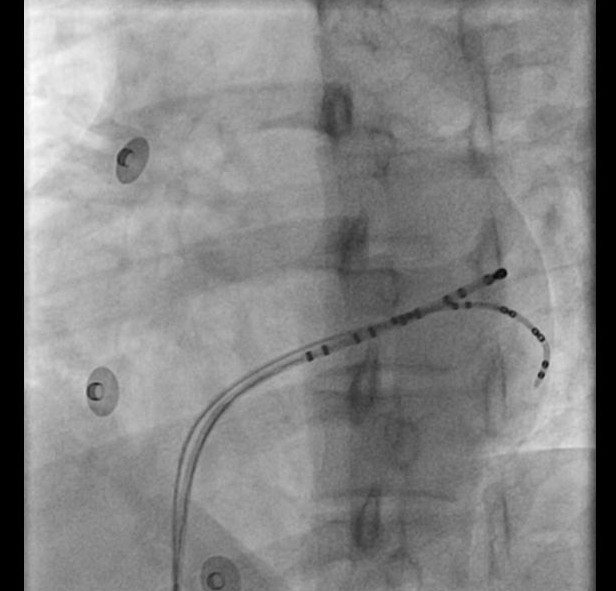

Stability

• Sheath

• Catheter course

• Retrograde approach

• Pacing if possible

• Entrain if during tachycardia